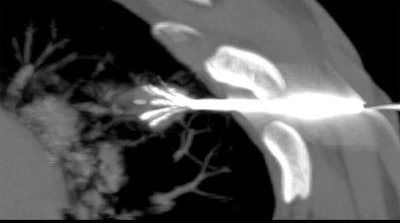

![]() |

| Above and below: Three-dimensional reconstructions of multidetector spiral CT datasets show correct placement of the radiofrequency needle into the tumor. Images courtesy of Dr. Riccardo Lencioni. |

The procedure was conducted under conscious sedation or general anesthesia, using an RFA device consisting of a 150-watt generator, temperature monitor, and expandable multitined electrodes (Starburst XL, RITA Medical Systems, Mountain View, CA).

"The concept was to destroy 1 cm of pulmonary tissue all around the tumor. This is why we deployed a maximum 5-cm (ablation target for) a lesion size of 3 cm" (1.0-3.0 cm, mean 2.2 cm ± 7), Lencioni said. "The RFA protocol, in terms of the time and temperature, was prolonged as much as 27 minutes to ensure full ablation of the 5-cm sphere."